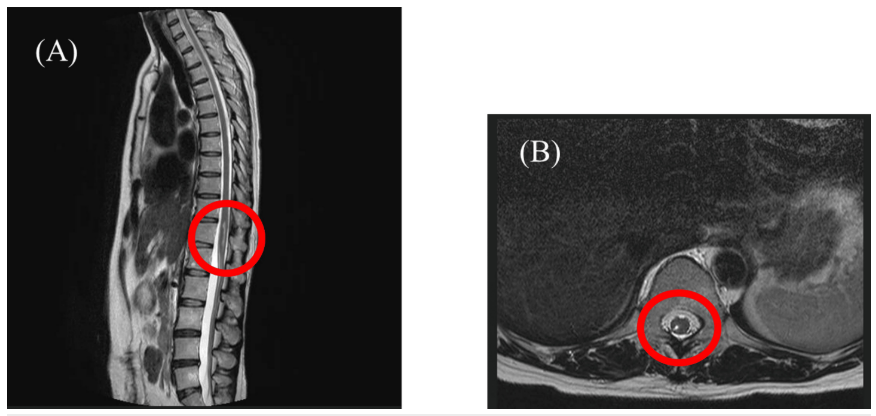

患者為49歲女性(身高151cm,體重53kg,BMI 23.24),主訴右下肢疼痛伴麻木。2021年12月因結(jié)腸癌行腹腔鏡結(jié)腸切除術(shù)時(shí)接受硬膜外麻醉,術(shù)中出現(xiàn)右下肢電擊樣劇痛,術(shù)中至術(shù)后留置導(dǎo)管進(jìn)行鎮(zhèn)痛。硬膜外導(dǎo)管拔除后,右下肢持續(xù)存在疼痛及麻木癥狀。T2加權(quán)磁共振成像(MRI)通過高信號(hào)顯像反映組織損傷及水腫導(dǎo)致的水含量增加,本病例顯示胸腰段脊髓損傷伴第12胸髓區(qū)域積液。因治療后癥狀持續(xù)存在,患者于2022年5月轉(zhuǎn)至疼痛科就診。既往史除結(jié)直腸癌及卵巢囊腫治療史外無特殊。初診時(shí)患者自訴右大腿至膝關(guān)節(jié)疼痛,靜息狀態(tài)下數(shù)字評(píng)定量表(Numeric Rating Scale, NRS)評(píng)分為7/10,發(fā)作時(shí)達(dá)10/10。步態(tài)跛行,行走時(shí)疼痛最為劇烈。查體發(fā)現(xiàn)右下肢肌力減退,踝關(guān)節(jié)背屈偶發(fā)困難。胸腰椎MRI顯示T11-T12脊髓水平(右后角至后索)水腫,未見其他脊髓病變或畸形。 脊髓于T11-T12胸椎水平(右后角至后索)呈現(xiàn)水腫影像,未檢出其他腰椎病變。(A)矢狀面觀;(B)橫斷面觀 基于硬膜外麻醉相關(guān)脊髓損傷后疼痛的初始判斷,但根據(jù)患者右大腿至膝關(guān)節(jié)的局部癥狀(L3神經(jīng)根支配區(qū)),修正診斷為神經(jīng)根性疼痛。經(jīng)硬膜外阻滯聯(lián)合L3神經(jīng)根阻滯治療后,疼痛程度由NRS 5分降至1分,麻木感及足趾不適持續(xù)存在,但步態(tài)有所改善。該神經(jīng)根阻滯療效僅能維持1-3個(gè)月。后續(xù)啟用普瑞巴林(175mg)聯(lián)合度洛西?。?0mg)治療,疼痛獲得中度緩解(NRS約3分)。鑒于既往治療僅能暫時(shí)緩解癥狀,患者于初診后14個(gè)月接受脊髓電刺激療法(SCS),電極置入T8-T9椎體上緣水平。該治療顯著改善疼痛癥狀,使患者得以開展康復(fù)訓(xùn)練并恢復(fù)日?;顒?dòng)。病程示意圖顯示:自初診起除藥物治療外,雖實(shí)施多種神經(jīng)阻滯但均未獲得持久療效;SCS植入14個(gè)月后,疼痛程度穩(wěn)定于NRS 3分水平。